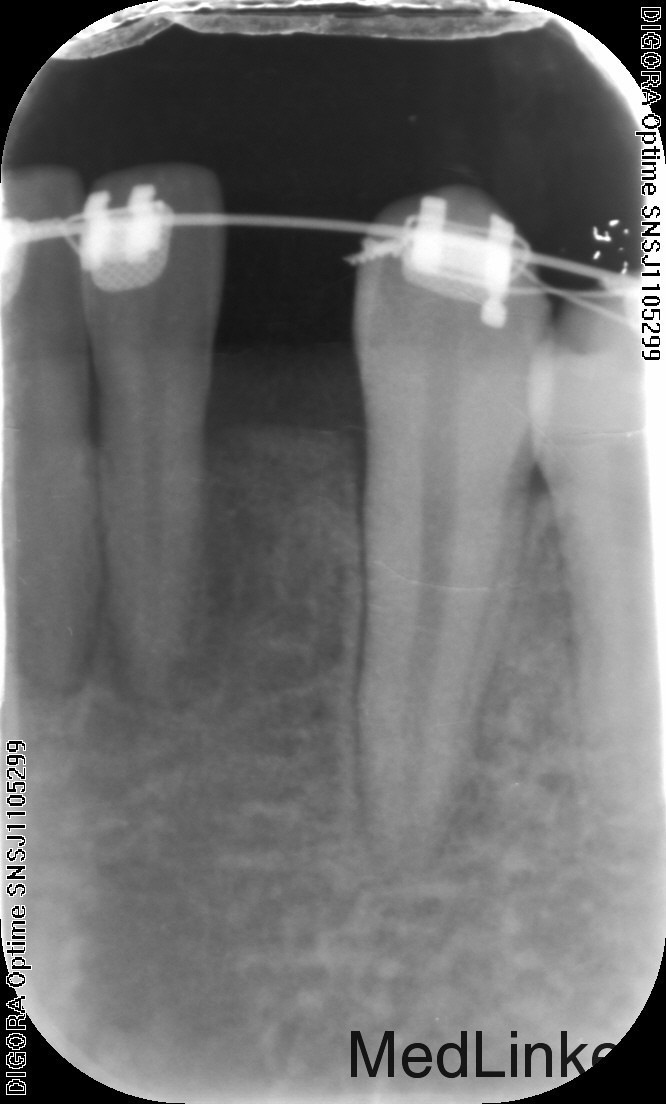

治疗:1、联合正畸科治疗,正畸科移动双侧中切牙至中线两侧后留出位置行种植治疗 2、常规消毒铺巾局部麻醉,切开翻瓣,植入Astra种植体3.0*8mm种植体两枚,严密缝合